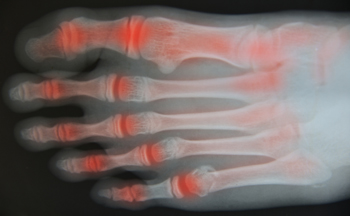

Walking May Help With Symptoms of Arthritis

Research has suggested that walking may be one of the best methods to manage the symptoms of pain, stiffness, or inflammation that can coincide with arthritis. It is important to start off slowly by building a walking routine, and with some time and experience, it should become easier when performed every day. Walking can also be beneficial for losing weight which may help lessen the stress that the joints endure. Slowly increasing the frequency, intensity, and length of time that you walk is the preferred method and can help to alleviate the aches and pain from arthritis. Many patients find that counting how many steps they take every day can help track their daily progress for maximum benefits. If you have arthritis in your feet, it is strongly suggested that you consult with a podiatrist who can offer you proper management techniques.

Research has suggested that walking may be one of the best methods to manage the symptoms of pain, stiffness, or inflammation that can coincide with arthritis. It is important to start off slowly by building a walking routine, and with some time and experience, it should become easier when performed every day. Walking can also be beneficial for losing weight which may help lessen the stress that the joints endure. Slowly increasing the frequency, intensity, and length of time that you walk is the preferred method and can help to alleviate the aches and pain from arthritis. Many patients find that counting how many steps they take every day can help track their daily progress for maximum benefits. If you have arthritis in your feet, it is strongly suggested that you consult with a podiatrist who can offer you proper management techniques.

Arthritis can be a difficult condition to live with. If you are seeking treatment, contact Ambrose Su, DPM from Cascade Foot Clinic. Our doctor can provide the care you need to keep you pain-free and on your feet.

Arthritic Foot Care

Arthritis is a term that is commonly used to describe joint pain. The condition itself can occur to anyone of any age, race, or gender, and there are over 100 types of it. Nevertheless, arthritis is more commonly found in women compared to men, and it is also more prevalent in those who are overweight. The causes of arthritis vary depending on which type of arthritis you have. Osteoarthritis for example, is often caused by injury, while rheumatoid arthritis is caused by a misdirected immune system.

Symptoms

- Swelling

- Pain

- Stiffness

- Decreased Range of Motion

Arthritic symptoms range in severity, and they may come and go. Some symptoms stay the same for several years but could potentially get worse with time. Severe cases of arthritis can prevent its sufferers from performing daily activities and make walking difficult.

Risk Factors

- Occupation – Occupations requiring repetitive knee movements have been linked to osteoarthritis

- Obesity – Excess weight can contribute to osteoarthritis development

- Infection – Microbial agents can infect the joints and trigger arthritis

- Joint Injuries – Damage to joints may lead to osteoarthritis

- Age – Risk increases with age

- Gender –Most types are more common in women

- Genetics – Arthritis can be hereditary

If you suspect your arthritis is affecting your feet, it is crucial that you see a podiatrist immediately. Your doctor will be able to address your specific case and help you decide which treatment method is best for you.

How to Care for Your Arthritic Foot

Arthritis is an inflammation of the joints and it can occur at any joint in the body, especially in the foot. It generally effects those who are older, however, it can occur at any age. Although there are many different forms of arthritis, there are three main types that occur in the foot. The three types are osteoarthritis, rheumatoid arthritis, and gout.

The primary cause of osteoarthritis is aging. As you age, cartilage degenerates around the joints which causes friction and pain. Obesity can cause osteoarthritis through mechanical stress. Injuries that damage joints can increase the probability as well. Finally, a family history of osteoarthritis can also increase chances of having it.

Rheumatoid arthritis occurs when the immune system attacks the joint linings and weakens them over a long time. While there is no known cause of rheumatoid arthritis, obesity and smoking can increase your chances of getting it. Women are also more likely to get it than men.

Gout is a form of arthritis that occurs when there is too much uric acid in your blood and painful crystals form in your joints. Men are more likely to have gout than women. People who are obese or drink alcohol often are also more likely to develop gout. Furthermore, having diabetes, heart disease, high blood pressure, high cholesterol, gastric bypass surgery or a family history of gout may increase your likelihood of developing the condition.

Symptoms of arthritis include pain, stiffness, swelling in the joints. These symptoms can make it harder and more painful to walk. Physical activity can increase pain and discomfort. Furthermore, joint pain can worsen throughout the day for osteoarthritis. Gout attacks generally last several days with the first few being the worst.

Diagnosis of gout includes either a joint fluid test or a blood test. X-ray imaging can detect osteoarthritis but not gout. On the other hand, there is no blood test for osteoarthritis. Rheumatoid arthritis is difficult to diagnosis. Doctors utilize family and personal medical history, a physical examination, and antibody blood tests to determine if you have rheumatoid arthritis.

Treatment varies for the different kinds of arthritis. Anti-inflammatory medication or steroids can help reduce pain from inflammation of the joints. Changing shoe types can help with some symptoms. Wider shoes can help with discomfort from gout and osteoarthritis. High heels should be avoided. Shoes with proper arch support and that take pressure off the ball of the foot can help with rheumatoid arthritis. Drinking lots of water can also help rid uric acid from the blood. Losing weight, improving your diet, and limiting alcohol and smoking can also help prevent or lessen the symptoms of arthritis.

If you are having trouble walking or pain in your feet, see a podiatrist to check if you have arthritis.